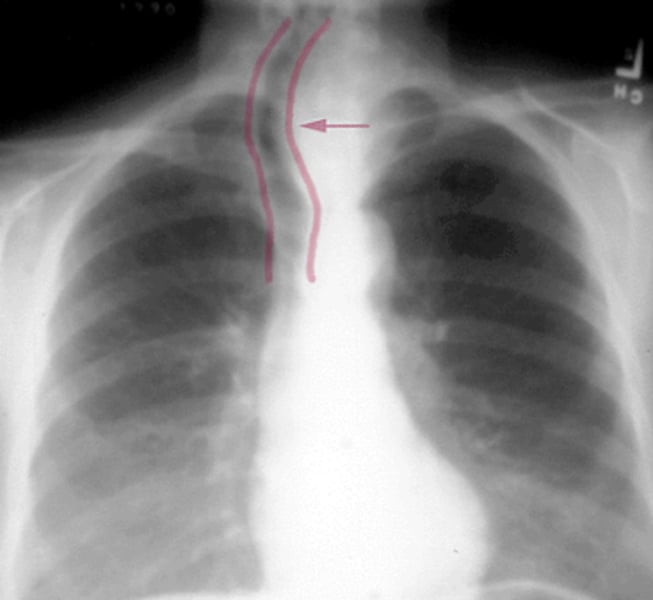

trachial deviation

a shifting of the trachea to either side of the midline of the neck caused by pneumothorax

<p>a shifting of the trachea to either side of the midline of the neck caused by pneumothorax</p>